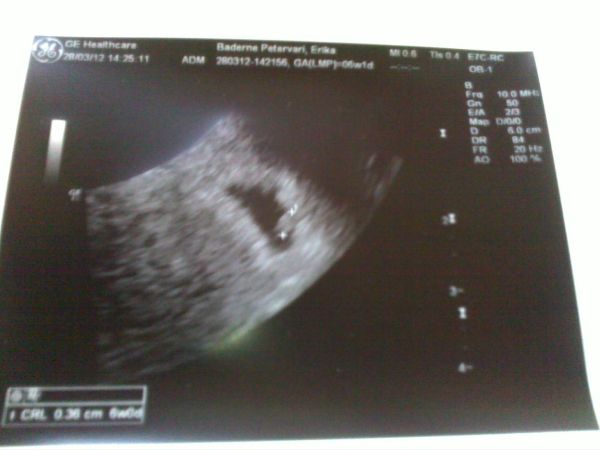

Era: Na igen! Ez az UH jobb minőségű képet csinál, mint Paragié. :D Mire kinyomtatta, addigra már nem is látszódott törpike, pedig a monitoron még ott volt. :lol: CSODASZÉP!!!!! Nekünk a jövő héten lesz szívhang, de csak 2 hét múlva megyek vissza UH-ra az a biztos.